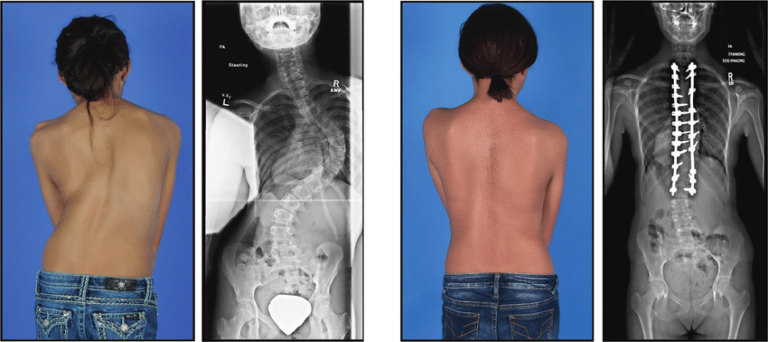

TAHUN BARU, KEBIASAAN BARU: MEMPERTAHANKAN KESADARAN BERPOSTUR UNTUK MENCEGAH PERTAMBAHAN KELENGKUNGAN TULANG BELAKANG PADA PENDERITA SKOLIOSIS

MITOS DAN FAKTA MENGEJUTKAN TENTANG SKOLIOSIS PADA ANAK DAN TERAPI SKOLIOSIS YANG EFEKTIF

SKOLIOSER BOLEHKAH BEROLAHRAGA? PANDUAN OLAHRAGA YANG COCOK UNTUK PENDERITA SKOLIOSIS